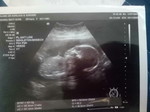

saya dah pregnant 6 minggu tapi setakat ni x rasa apa² mual² pening² normal ka tu?maaf ni my first pregnancy